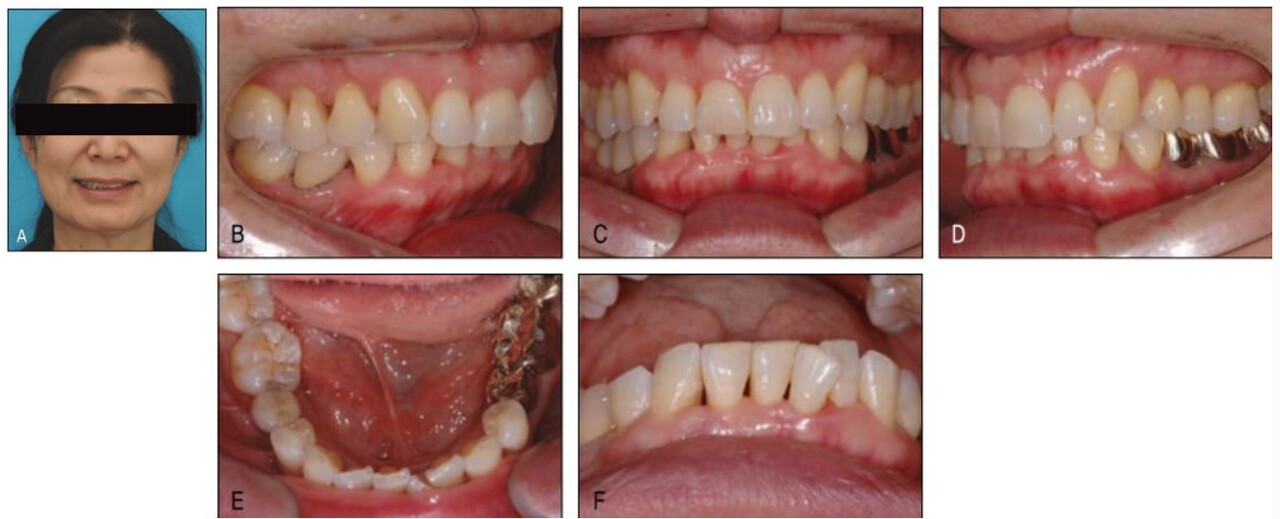

젊었을 때는 전혀 멋을 부리지 않았던 분들도 고령자가 되어서 얼굴의 점이나 검버섯을 빼고자 하는 것을 주위에서 흔히 볼 수 있는데, 같은 맥락에서 좀더 젊게 보이기 위해 또는 좀 더 젊어지기 위해 치과를 찾는 고령자들이 늘어날 것으로 전망하고 있다 (그림 23-3, 4).

이러한 young-looking appearance를 위한 치과치료로 과거에는 보철치료가 주로 행해졌으나, 전술한 바와 같이 자연치 보존에 대한 사회 전체적인 관심증가로 자연치 발치없이 행할 수 있는 유일한 심미치료인 교정 치료에 대한 수요가 증가하고 있다.

이전에는 이러한 rejuvenation 치료를 위해 교정치료를 찾는 대부분이 50대이었으나 최근에는 인구의 고령화와 기대수명의 연장으로 인해 60대, 70대 환자 또한 급증하고 있다.